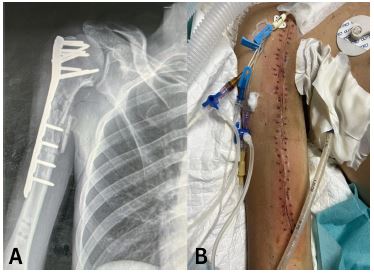

A 43-year-old male presented with multiple injuries sustained from a bomb explosion. He had a head injury and a Glasgow Coma Scale (GCS) score of 8, a chest injury with haemopneumothorax, and a Gustilo-Anderson Grade IIIB open fracture of the right proximal humerus with no signs of neurovascular injury of the right upper limb. He was intubated in the ED and subsequently underwent a craniotomy, bilateral intercostal chest tube insertions, and Open Reduction Internal Fixation (ORIF) of the humerus. This ORIF failed due to an inappropriate plate length and was later revised on another occasion with the correct plate followed by soft tissue repair and covering of the bone and plate with a SSG. The intercostal tube was removed after 6 days. He was admitted to the Intensive Care Unit (ICU) for 4 weeks after which weaning from mechanical ventilation was successful and he was transferred to a normal word.

Figure 2: (A) Anteroposterior view radiograph of the fracture and internal fixation. (B) Clinical photograph of the healed wound.

A 22-year-old male presented with a traumatic brain injury, a right-sided haemothorax, and a Gustilo-Anderson Grade III open fracture of the right proximal humerus caused by a gunshot injury. The patient received intercostal tube drainage and underwent ORIF (Figure 3A), primary wound closure, and received a course of IV Ceftriaxone. He was admitted to the ICU for 3 weeks and the wound was found to have healed by week 2 (Figure 3B). Unfortunately, the patient failed trials of extubation and passed away on week 4.

Figure 3: (A) Anteroposterior view radiograph of the comminuted fracture of the right proximal humerus with plate and nails visible in situ. (B) Clinical photograph of the healed wound.